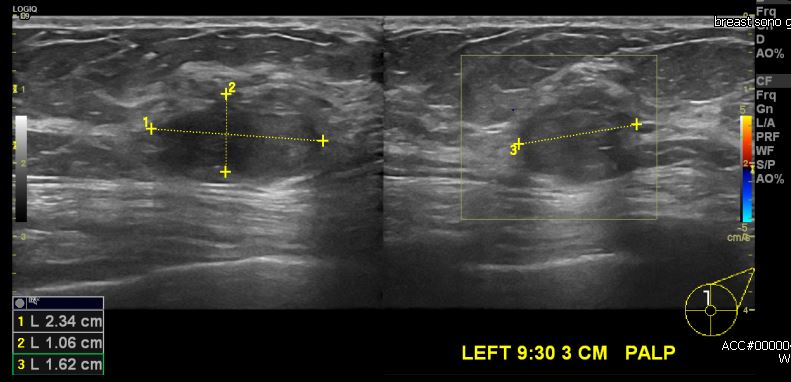

상기환자 건강검진상 이상소견으로 내원한 60대 여성분으로 좌측 9시 30분 방향에 만져지는 혹 조직검사 시행하였고, 좌측 유방에 점액암 진단되었습니다.